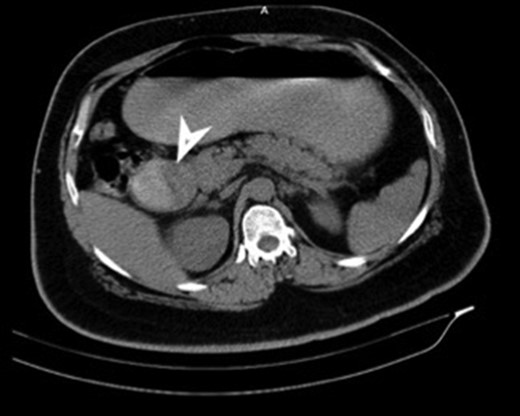

CT (transverse) image showing first and second part of duodenum filled with a mass lesion.

| Case 1 | 30/M | 3 months | Vomiting, Malena | Well defined rounded hypodense submucosal lesion in second part of duodenum (Fig. 1) | Smooth mucosal bulge likely due to submucosal lesion in D2 with difficulty in negotiating scope beyond (Figs 2 and 3) | Normal duodenal mucosal fragments with mild lympho-mono nuclear cell infiltrate in the lamina propria | Pancreaticoduodenectomy | 2 | 2 days | 6 |